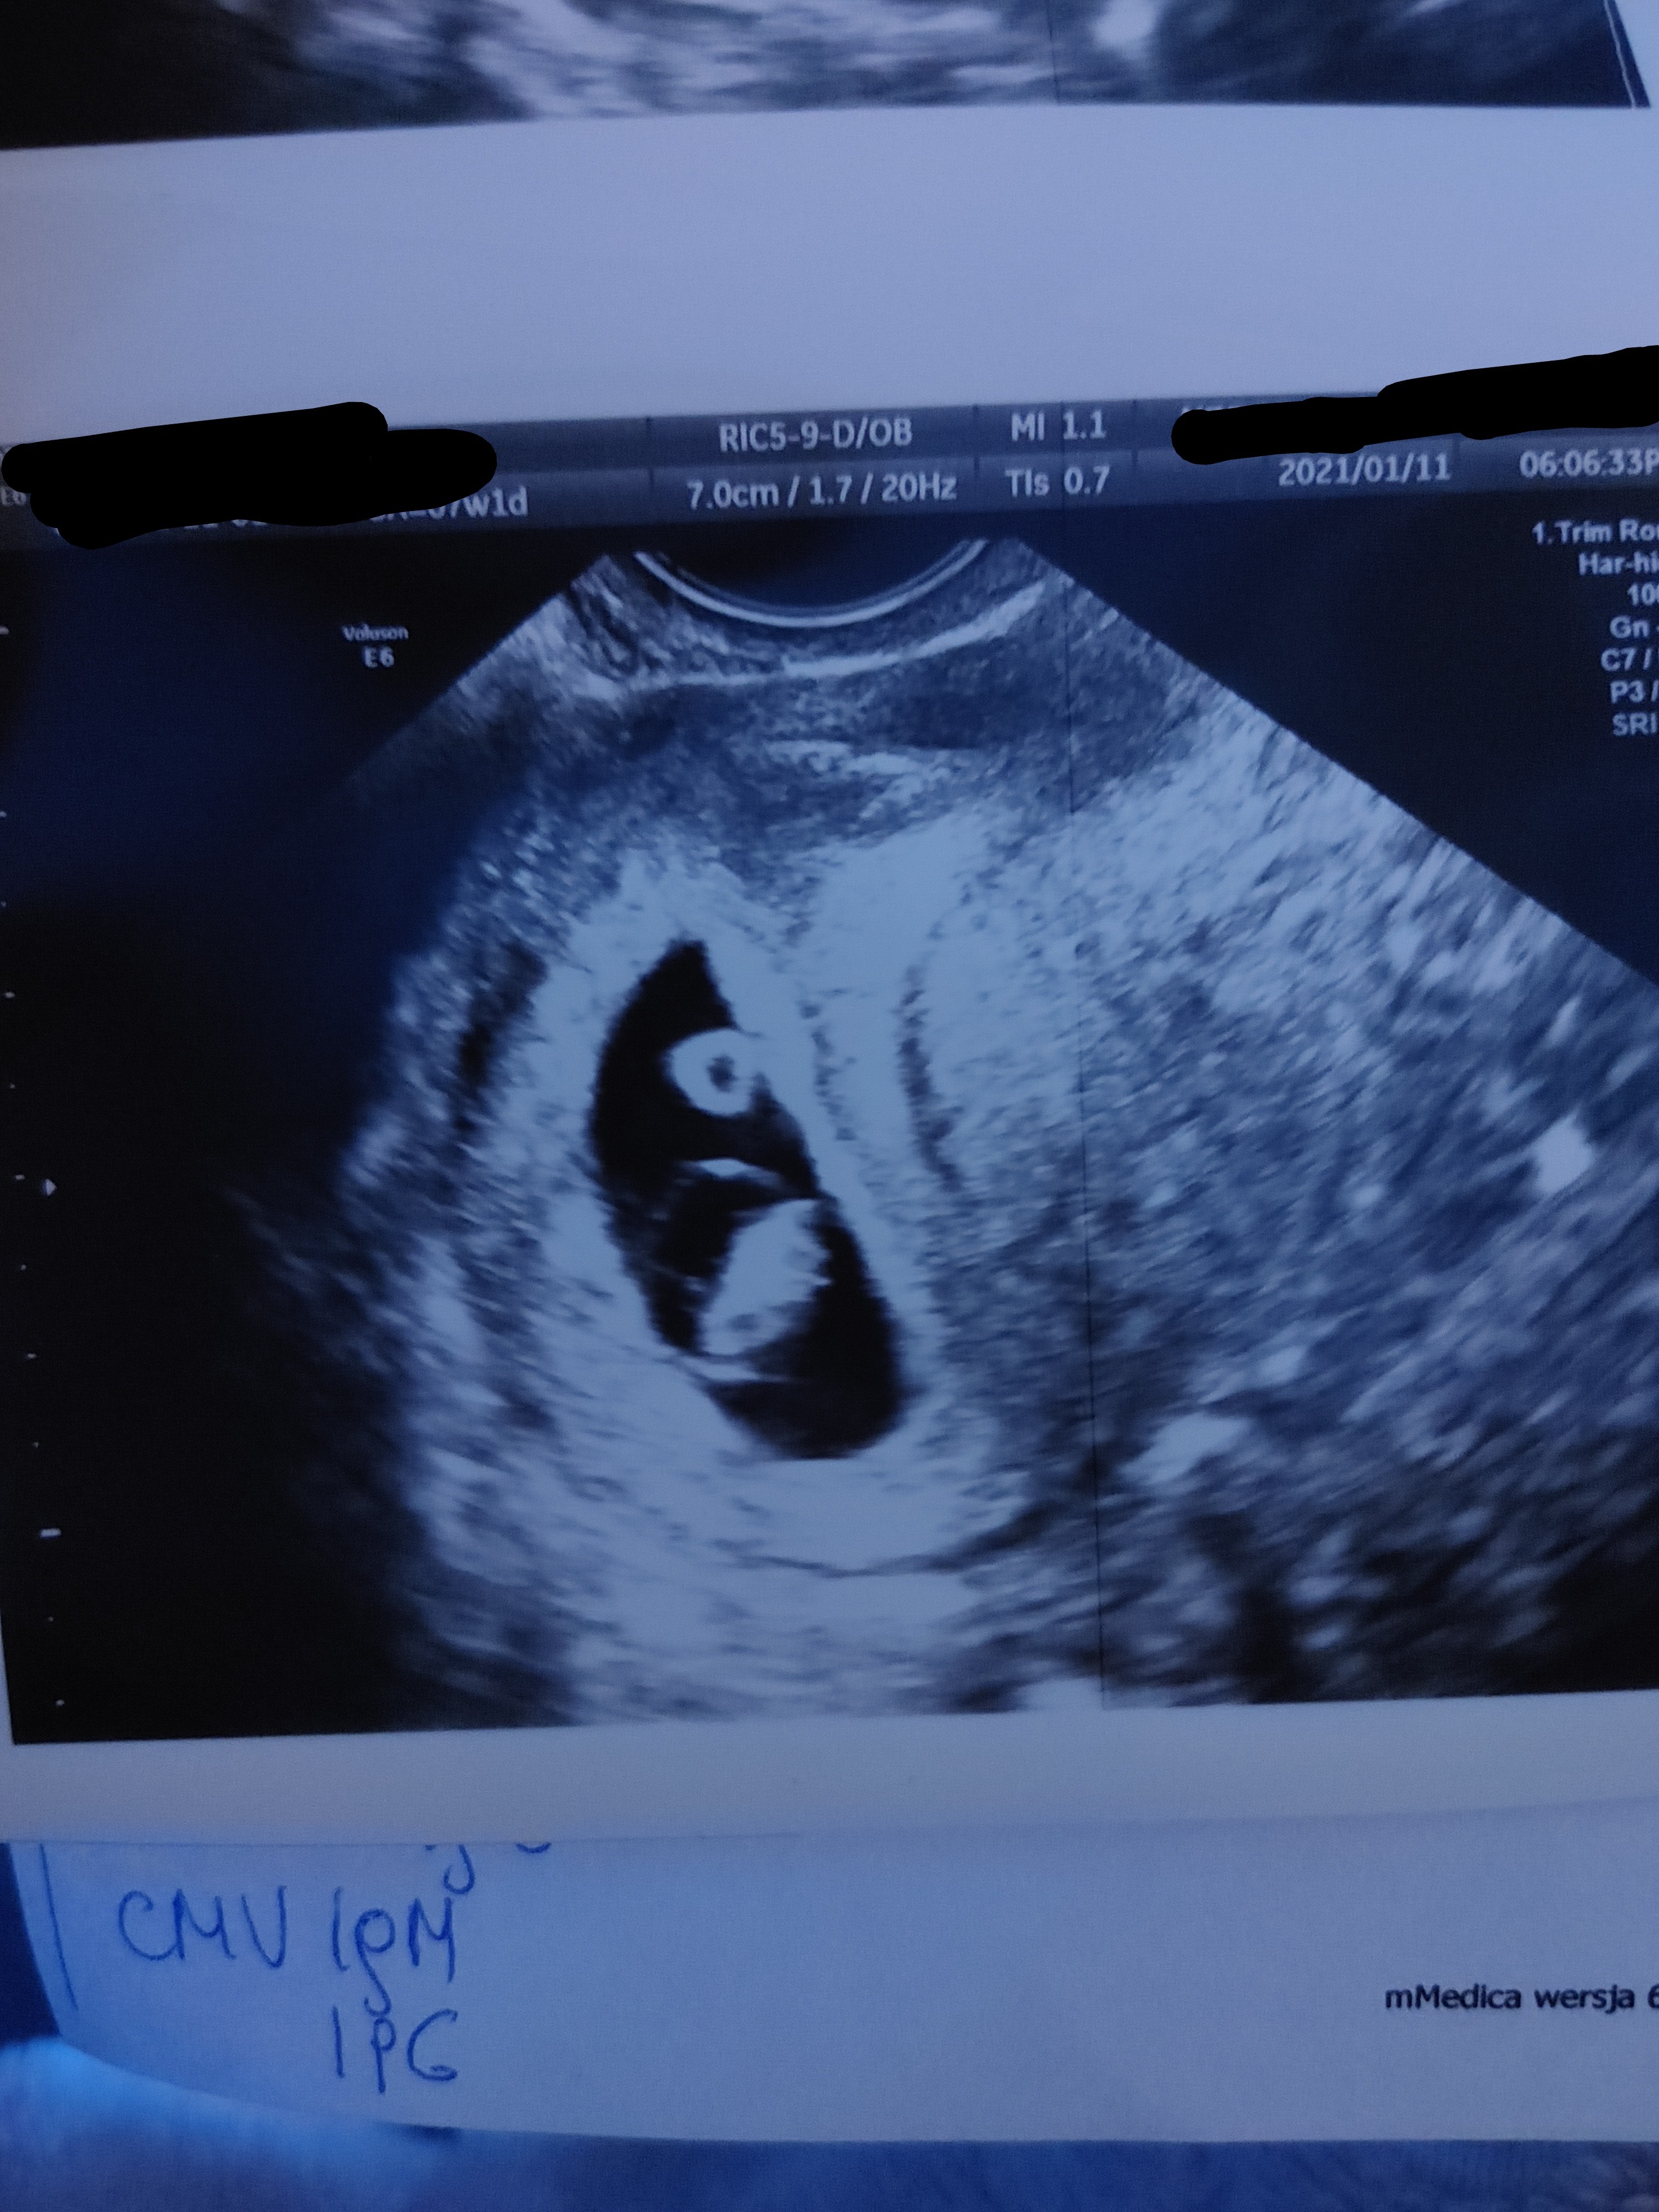

W tamtym tygodniu 0,35 cm, a w tym tygodniu już 1,19 cm - rośniemy

serduszko 140ud/min. Wstawiam foteczkę